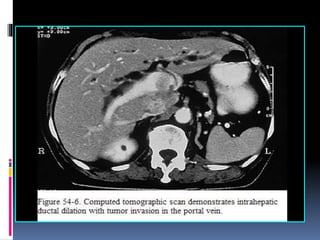

Cholangiocarcinoma Intra-hepatic Disease  Suspiciousmass on CT. Quadruple phase CT with 0.5 cm cuts through the liver and portal hepatitis. Consider CTA reconstruction. Treatment  If adenoncarcinoma: look for primary with a chest CT and upper/lower endoscopy.  Colon, pancreas, and stomach are common primary sites.